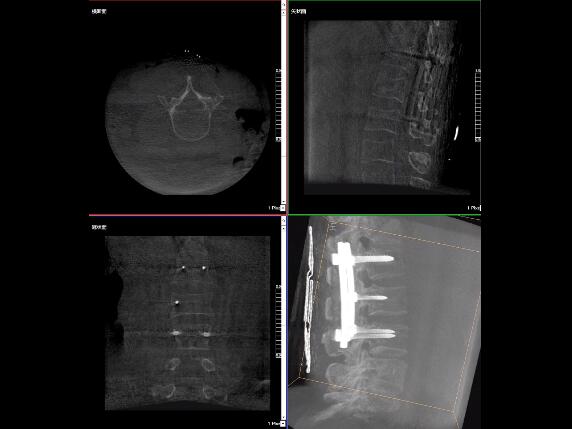

比如,醫(yī)生在做PKP(椎體成形術)的時候,或者在置入螺釘?shù)臅r候,醫(yī)生需要在影像上看到螺釘打進去的進針點以及進針的路徑。比如,我們在打腰椎的釘子時需要看到“貓眼”。我們只有把釘子完全打在“貓眼”里面,才能確保釘子打在了椎弓根里,所以對“貓眼”的顯影就非常重要。

“貓眼”指的是椎弓根在正位的投影。

最后我要強調一點,以上我提到的“貓眼”,在二維的X光片上,醫(yī)生是靠經(jīng)驗去判斷釘子是否打在椎弓根里,這個時候如果我們的設備再先進一點,診斷手段再多一點,如果我們能夠把二維的影像轉換為三維的影像,可能就不會完全依賴醫(yī)生的經(jīng)驗。

我們可以在三維的圖像中直觀的看到釘子到底在不在椎弓根里面,這樣可以指導我們準確的進針,指導我們進行一場高質量的手術,可以起到事半功倍的效果,手術會簡單得多,病人的預后也會好得多。